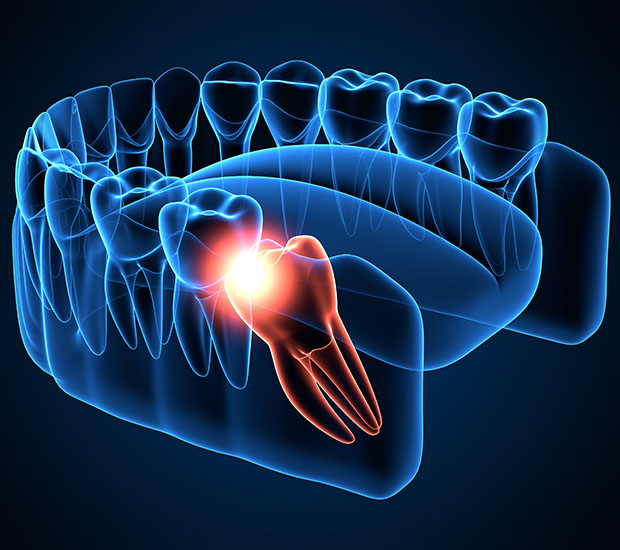

Wisdom teeth extraction can help to relieve pain in a patient's teeth that results from the wisdom teeth causing crowding issues or growing incorrectly. There are many different reasons you may need to extract your wisdom teeth. Wisdom teeth extraction removes the third set of molars in the back of your mouth.

"Wisdom teeth" is the colloquial term for the third set of molars that sit in the back of the mouth. They are called such because they come between the more "mature" ages of 17 and 21. The emergence of wisdom teeth can be uncomfortable, even if they are emerging correctly. Wisdom teeth do not always necessitate extraction. On the contrary, properly aligned wisdom teeth may assist in chewing.

However, if there is no adequate space for the wisdom teeth to emerge or if the teeth are coming through in the wrong position, they may become impacted (or trapped in the jaw or under the gums). This may cause cysts, damage to neighboring teeth, gum disease, infection, pain, tooth, decay, and tumors. A dentist needs to monitor the patient's wisdom teeth and determine the best course of action.